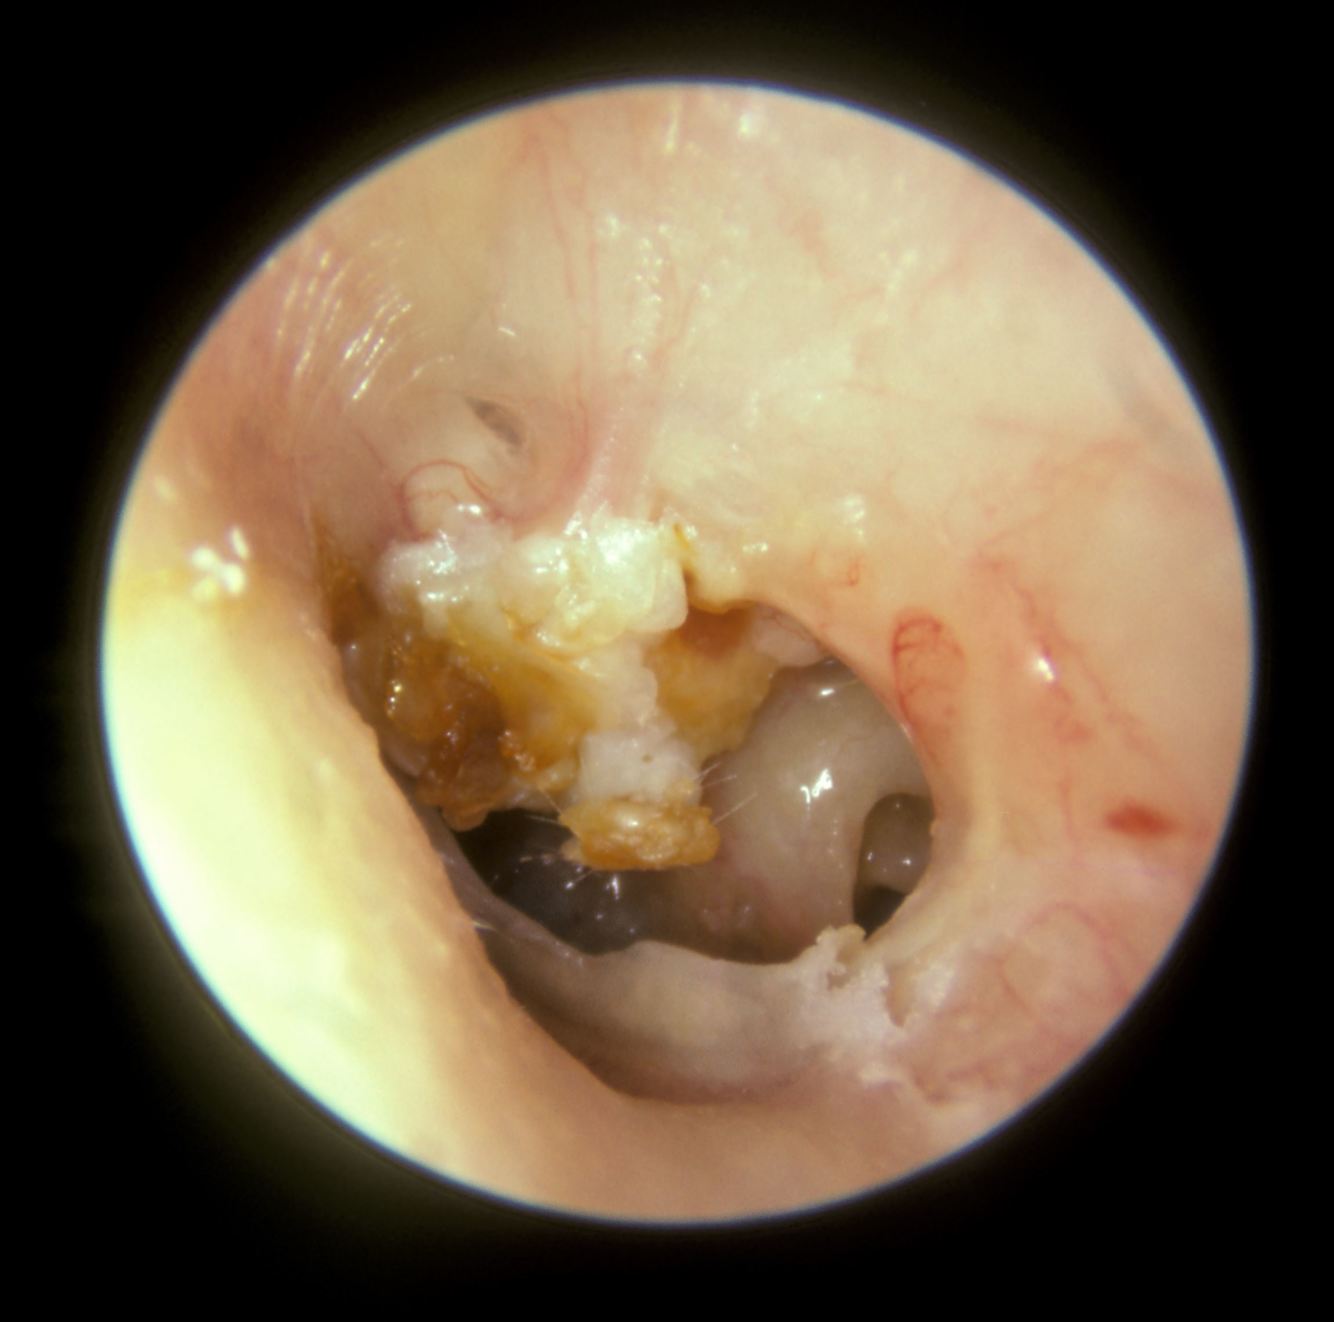

Why might cholesteatoma cause vertigo?

Breach of the otic capsule bone causing dizziness on pressure change transmitted from the middle ear to the vestibular system